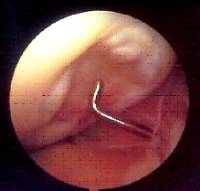

Existen diferentes opciones de tratamiento quirúrgico en función de la estabilidad y localización del fragmento osteocondral (microperforaciones bajo control artroscópico , fijación in situ del fragmento osteocondral , empleo de injertos osteocondrales / mosaicoplastia ).

En los casos evolucionados con desprendimiento del fragmento osteocondral es preciso retirar el cuerpo libre articular ("ratón" articular) .